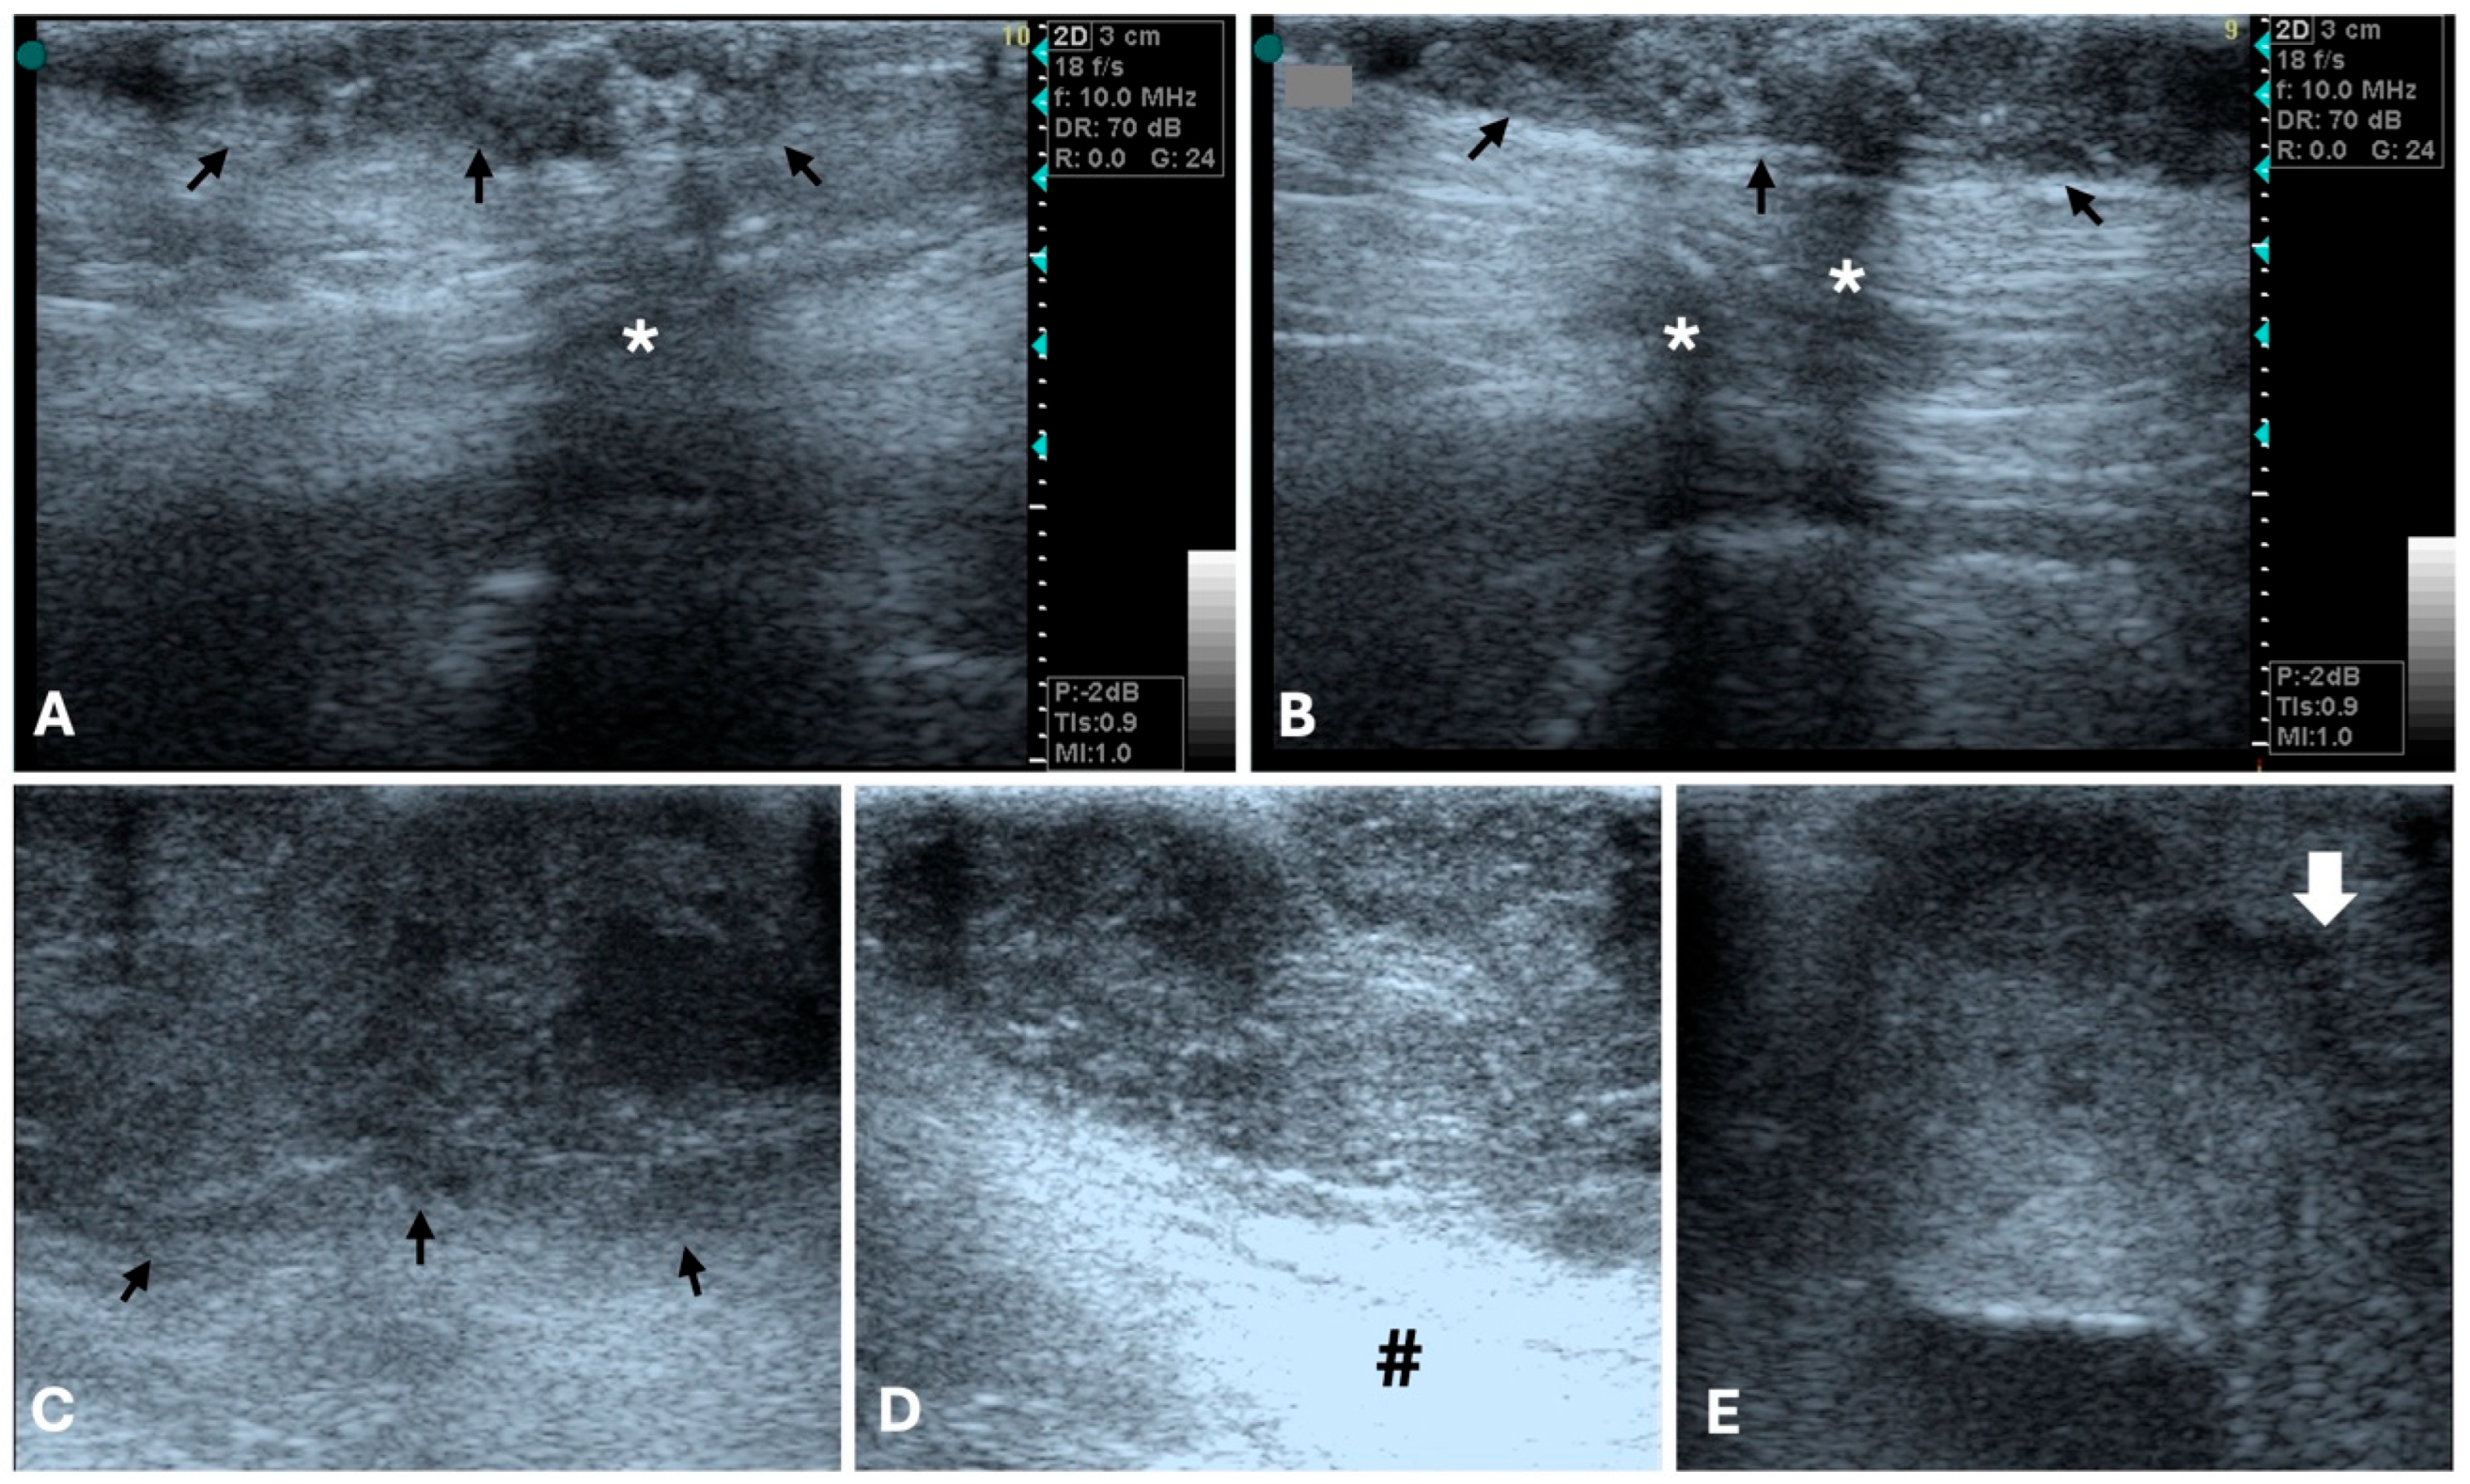

3.1. Ultrasonography

- Feliciano, M.A.R.; Vicente, W.R.R.; Silva, M.A.M. Conventional and Doppler Ultrasound for the Differentiation of Benign and Malignant Canine Mammary Tumours. J. Small Anim. Pract. 2012, 53, 332–337. [Google Scholar] [CrossRef] [PubMed]

- Nyman, H.T.; Nielsen, O.L.; McEvoy, F.J.; Lee, M.H.; Martinussen, T.; Hellmén, E.; Kristensen, A.T. Comparison of B-Mode and Doppler Ultrasonographic Findings with Histologic Features of Benign and Malignant Mammary Tumors in Dogs. Am. J. Vet. Res. 2006, 67, 985–991. [Google Scholar] [CrossRef] [PubMed]

- Soler, M.; Dominguez, E.; Lucas, X.; Novellas, R.; Gomes-Coelho, K.V.; Espada, Y.; Agut, A. Comparison between Ultrasonographic Findings of Benign and Malignant Canine Mammary Gland Tumours Using B-Mode, Colour Doppler, Power Doppler and Spectral Doppler. Res. Vet. Sci. 2016, 107, 141–146. [Google Scholar] [CrossRef]

| Vascularity (Color Doppler US) | Limited angiogenesis [75,81]. Peripheral vascular pattern [74,81] | Increased neovascularization [40,87]. Mixed vascular pattern [74,81] | Several studies report no significant differences in vascular flow [75,81,88], but in the distribution pattern [81] |

| CEUS | May have low specificity in differentiating benign/malignant tumors [40] | Shorter periods of contrast wash-in and peak enhancement times in complex carcinomas [40,77] | Could be a useful adjunct tool for assessing tumoral perfusion patterns |